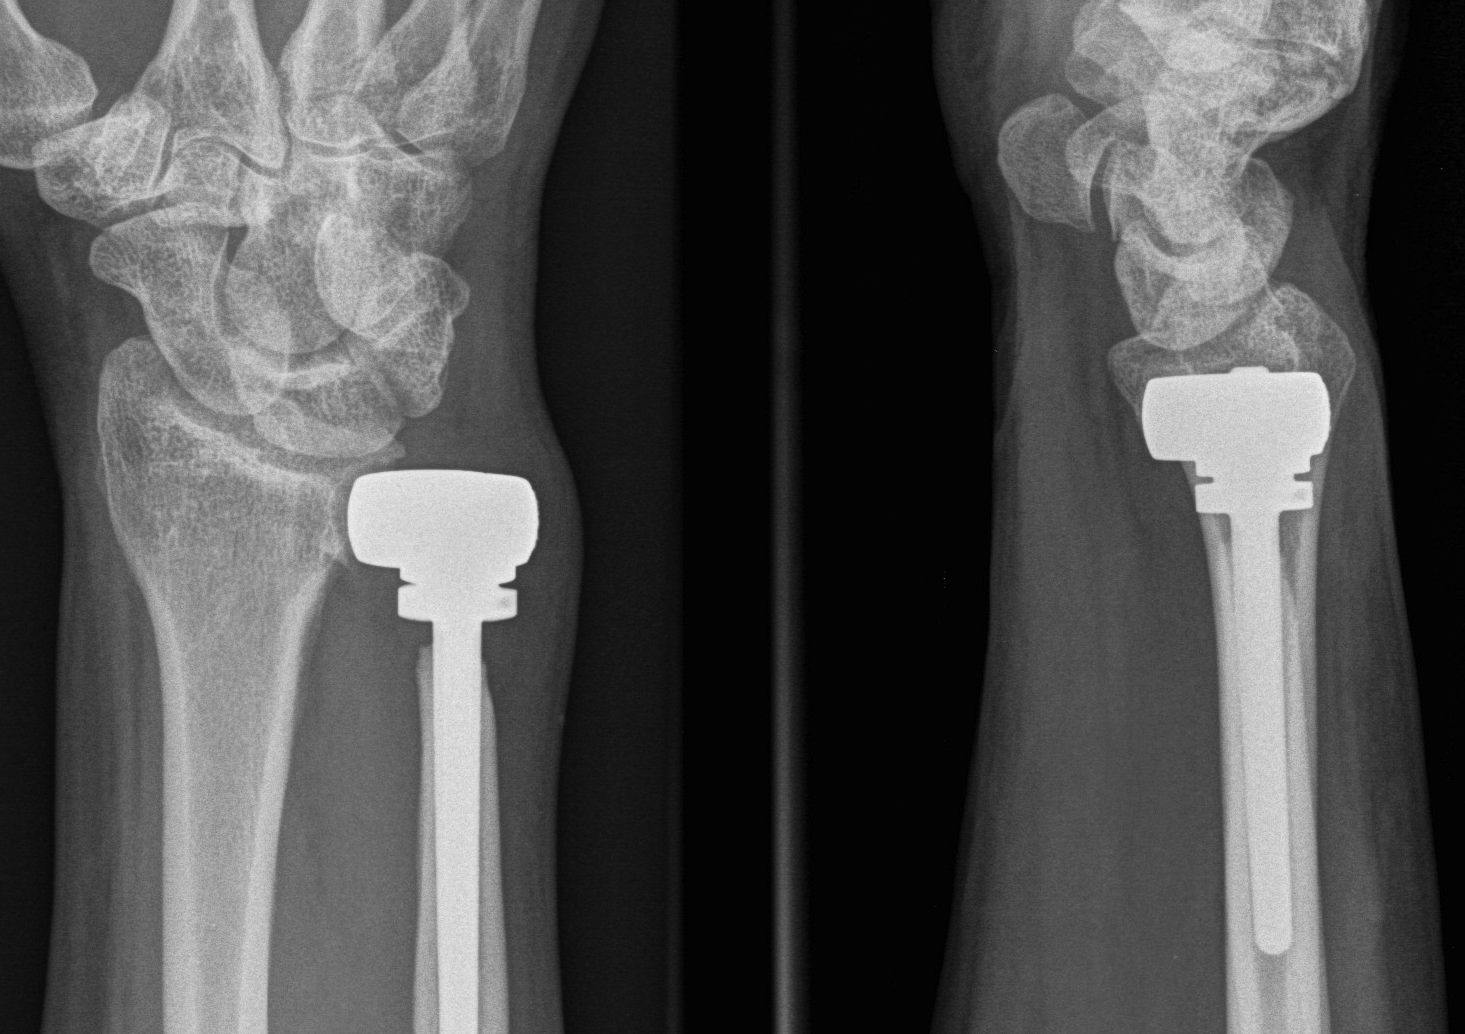

DRUJ Replacement

Options

Hemiarthroplasty

Total joint arthroplasty

DRUJ hemiarthroplasty

Technique total joint arthroplasty

Aptis DRUJ total joint arthroplasty